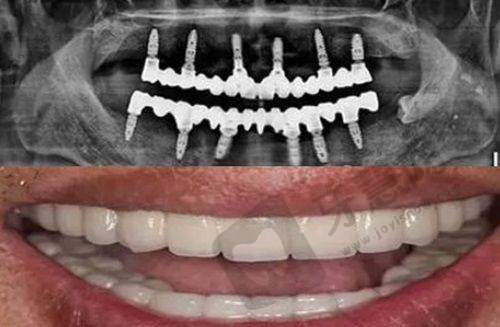

广州智仁口腔门诊部提供牙齿种植、牙齿美容修复、牙齿美白、牙齿矫正及口腔保健等综合性服务,还拥有多项特色项目,如微创拔牙和根管治疗。在设备方面,拥有口腔CBCT、热胶系统、根管机扩张器、口腔显微镜、超声骨刀、高频电刀、不痛牙周医疗器械、不痛麻醉装置等优质设备,这些精良的设备为口腔治疗提供了有力的技术支持。同时,门诊部致力于为患者提供高品质的口腔服务,注重患者的体验和感受。这些特色亮点都体现了广州智仁口腔门诊部的正规性和专精性。